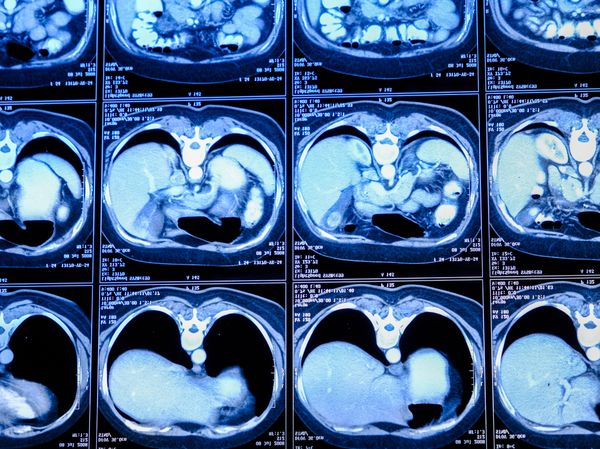

Novinář v domácnostiZdravíKolonoskopie – vyšetření střeva: strašák, který může zachránit i váš život1. prosince 2025